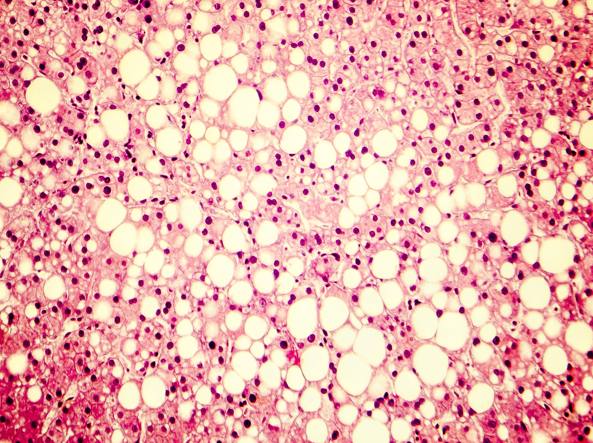

La steatosi epatica

Il fegato grasso è una condizione molto comune. Quando severa può comportare dei rischi per la funzione del fegato.